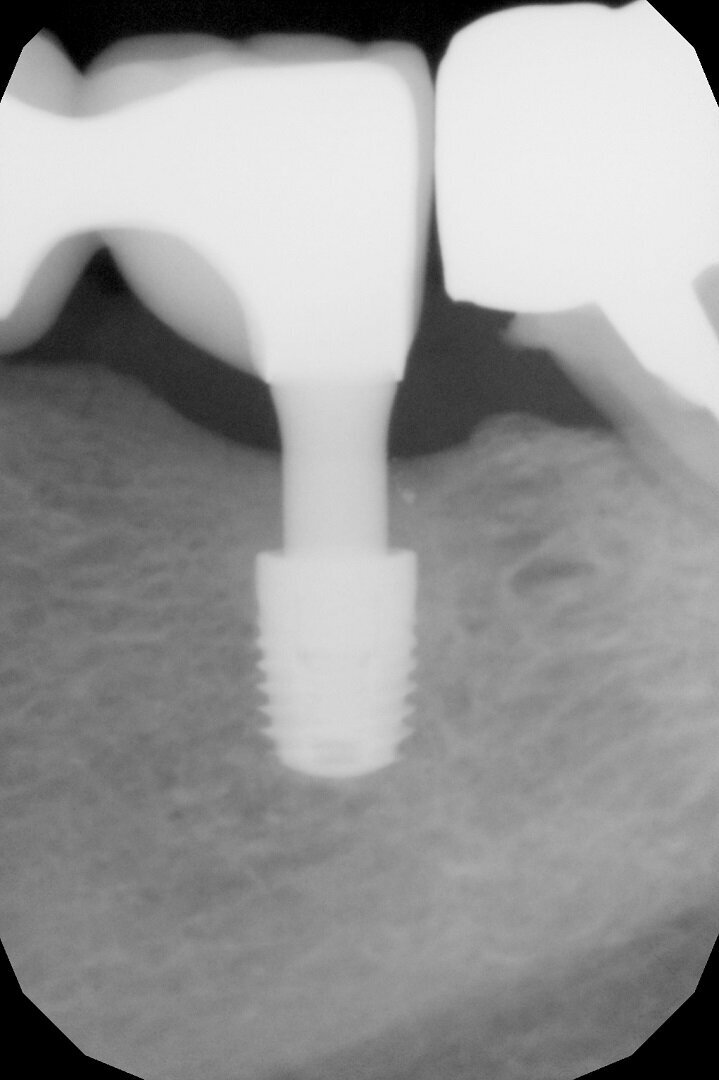

After 70 days, radiographic control was performed and the healing abutments were replaced with two easy abutments directly in order to comply with the one abutment, one time protocol (Fig. 4). The abutments were torqued to 30 Ncm according to the implant’s prosthetic protocol. This is necessary for the activation of the conical coupling between implant and abutment and for a sterile connection that prevents micro-movements and bacterial infiltration between implants and abutments in the sub-crestal area and the resulting bone resorption. Thereafter, we took a polyether impression on snap-on copings directly inserted on the abutments and fabricated a traditional cemented metal–ceramic bridge. In the following months, the patient initially underwent regular check-ups and professional hygiene, but thereafter kept extending the check-up times and neglecting her oral hygiene.

After three years, a panoramic radiograph was performed, highlighting excellent maintenance of the bone trophism and closure of the osteotomies created with the insertion of the implants (Fig. 5). Results of this type testify to the ideal biomechanical situation created above the implants, which are then protected from any bacterial infiltration, not only by the mucosa, which appeared stable and healthy, but also by the bone bridge created to protect the implant necks.

A further radiographic check was carried out seven years after the implants had been placed and showed growth of the bone level and the formation of a curved bone profile to support the interdental papillae, which is typical of natural teeth (Figs. 6a &b). Caries occurred under the crown of tooth #37, but the patient did not wish to have it treated. Upon physical examination, the soft tissue appeared stable and of excellent trophism.

After nine years, a new radiograph was performed which highlighted how the scallop had not only been maintained but even remodelled (Figs. 7a & b). The supra-implant bone appearance around the abutments presented a hyperdense and extreme continuity with the abutment neck, despite the non-punctual hygienic maintenance, highlighted by the state of the soft tissue and by the caries affecting tooth #37, then in the terminal stage (Figs. 8 & 9). After removal of the bridge, we tried probing, but it was absolutely impossible owing to the thickness of the soft tissue.